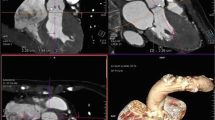

For all transcatheter valvular procedures, assessment of vascular access is important and relies on different imaging modality (Fig. 8.16). Absolute size, amount, and extent of calcification, as well as tortuosity of iliac and femoral artery determine suitability for the procedure [138, 139]. Vascular complications are the major cause of morbidity and mortality in patients undergoing TAVI, and this should therefore be considered as transcatheter valve procedures increase in number with an expansion toward lower-risk, younger patients.